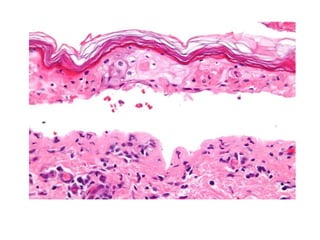

Este documento describe el síndrome de Stevens-Johnson y la necrólisis epidérmica tóxica (NET), dos enfermedades graves que afectan la piel y las mucosas. Se caracterizan por una reacción de hipersensibilidad que puede ser causada por medicamentos, infecciones virales o bacterianas, o factores idiopáticos. Los medicamentos son la causa más común, especialmente sulfonamidas, penicilinas y anticonvulsivantes. La suspensión rápida del agente causante es crucial para reducir la morbilidad